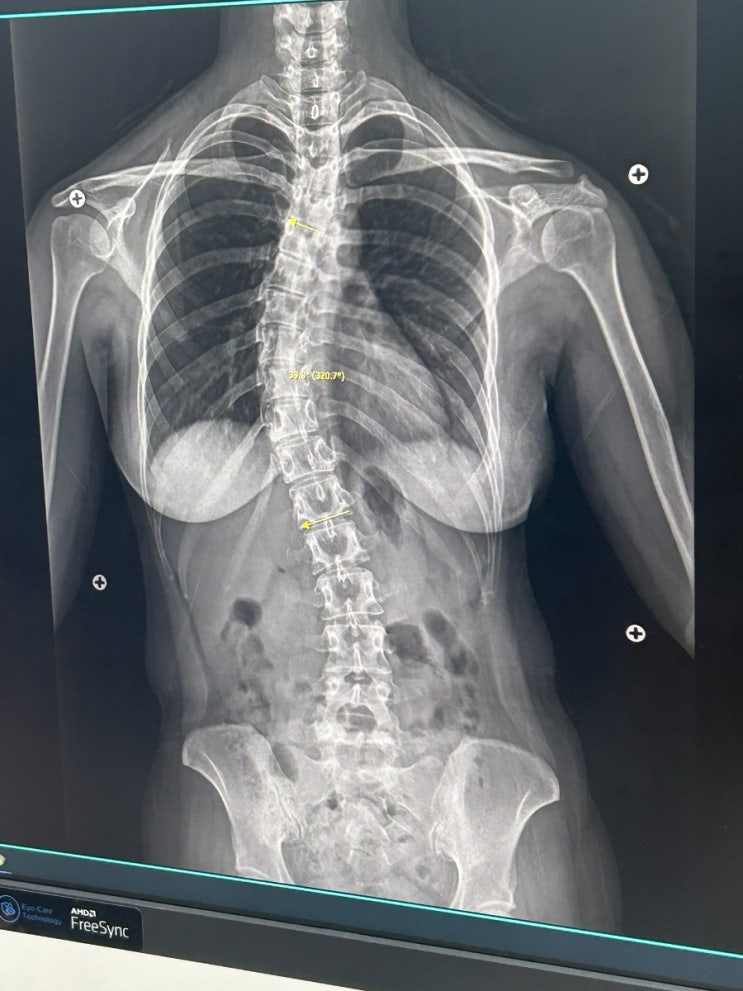

척추측만증 허리 통증 증상&내가 가장 효과 본 교정 운동법

"허리디스크 파열이 척추측만증으로?" 내 몸이 삐뚤어진 이유 & 스스로 완치한 기적 같은 후...